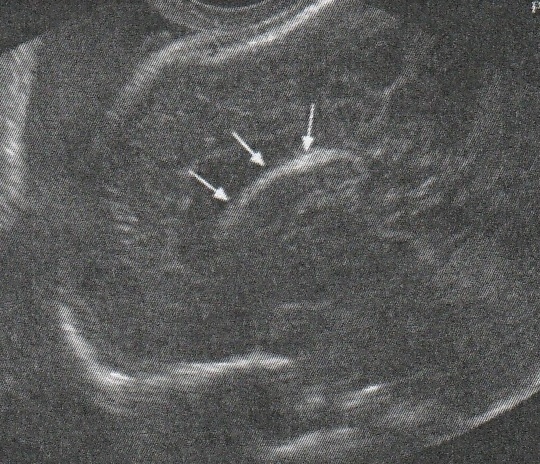

2016年8月4日在執行胎兒高層次超音波檢查時,我發現胎兒腦部的CSP(cavum septum pellucidum)很不清楚(附圖1~4),遇到這種情況,需要仔細評估胎兒腦部的駢胝體,因為CSP的天花板是駢胝體,CSP不明顯時,要合理的懷疑駢胝體沒有發育,或駢胝體下方有長東西(例如lipoma),駢胝體是連接左右大腦的神經纖維所組成。